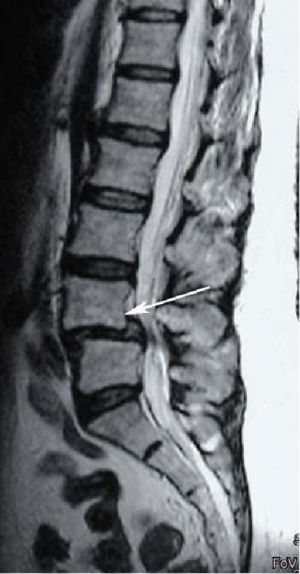

3. Дегенеративный листез.

Спондилолистез также классифицируется по степени смещения позвонка (по Meйердингу): смещение от 0 до 25% по отношению к нижележащему позвонку - I степень, от 25% до 50% - II степень, от 50% до 75% - III степень, от 75% до 100% - IV степень. Полное смещение позвонка по отношению к нижележащему называют спондилоптозом.

Кроме того, спондилолистез может быть стабильным и нестабильным. При нестабильном спондилолистезе позвонки смещаются при перемене положения пациента, например, при сгибании или разгибании. При стабильном листезе смещения не происходит. Для диагностики нестабильности позвоночно-двигательного сегмента выполняется функциональная спондилография, т.е. рентгенография поясничного отдела позвоночника с функциональными пробами: рентгеновский снимок выполняется в положении максимального сгибания и разгибания в поясничном отделе позвоночника. Это важно, т.к. если пациенту предстоит оперативное лечение, в случае нестабильности, операция выполняется с фиксацией позвонков титановой конструкцией.